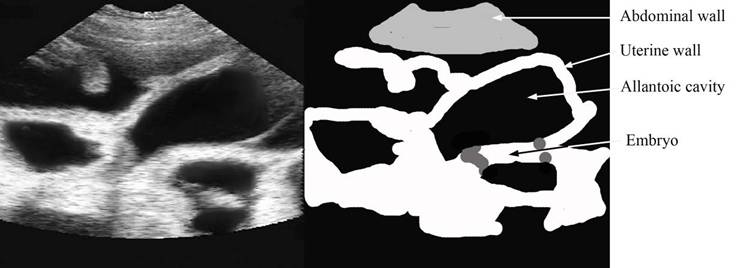

28 days pregnancy – vesicles easy to see – but note the embryo

repro draw 28 days gestations+ label copy.jpg